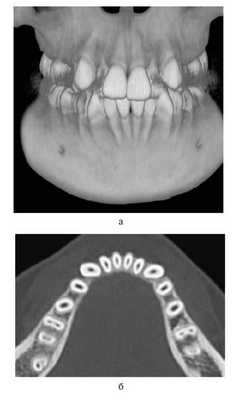

У всех обследованных выявили клиническое сужение зубных рядов и аномалии положения отдельных зубов, у 53 (42,1%) — обратную резцовую окклюзию, у 126 (100%) — деформацию окклюзионной плоскости. При анализе диагностических моделей челюстей и сопоставлении полученных результатов с показателями индивидуальной нормы у всех обследованных определялось статистически достоверное (р≤0,05) сужение зубных рядов разной степени.

Деформации зубоальвеолярных дуг устраняли до проведения костной пластики. Для этого использовали аппараты, которые позволяли нормализовать положение резцов, фрагментов АО, положение резцовой кости и в результате создать зубоальвеолярную дугу правильной формы и определить истинный размер расщелины (рис. 2).

Рис. 2. Несъемный дуговой аппарат (система «2×4»). а — динамика перемещения зубов у пациента с ОРГН; б — динамика перемещения зубов у пациента с ДРГН.

При изучении диагностических моделей зубных рядов после ортодонтического лечения в 1-й группе зарегистрировали расширение верхнего зубного ряда в области клыков на 4,8 мм; длина переднего отдела этого зубного ряда увеличилась на 4,4 мм. Во 2-й и 3-й группах произошло расширение верхнечелюстной зубной дуги в области премоляров на 2,1 мм, в области моляров — на 2,3 мм; длина переднего отдела зубного ряда увеличилась на 2,7 мм.

Нормализовалось положение резцов у 68 (54%) пациентов, положение резцовой кости в сагиттальной и трансверсальной плоскостях — у 40 (40%). У всех пациентов при ортодонтической подготовке к костной аутопластике достигнуто расширение верхнего зубного ряда.